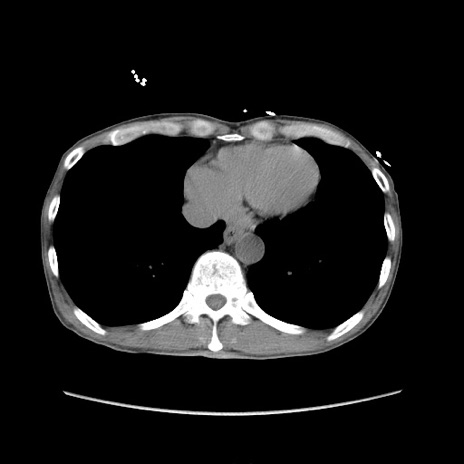

症例11(横断像)

【症例】 60歳代男性

【既往歴】 膀胱癌(膀胱全摘+尿管皮膚瘻術) 、胃癌術後

冠状断像